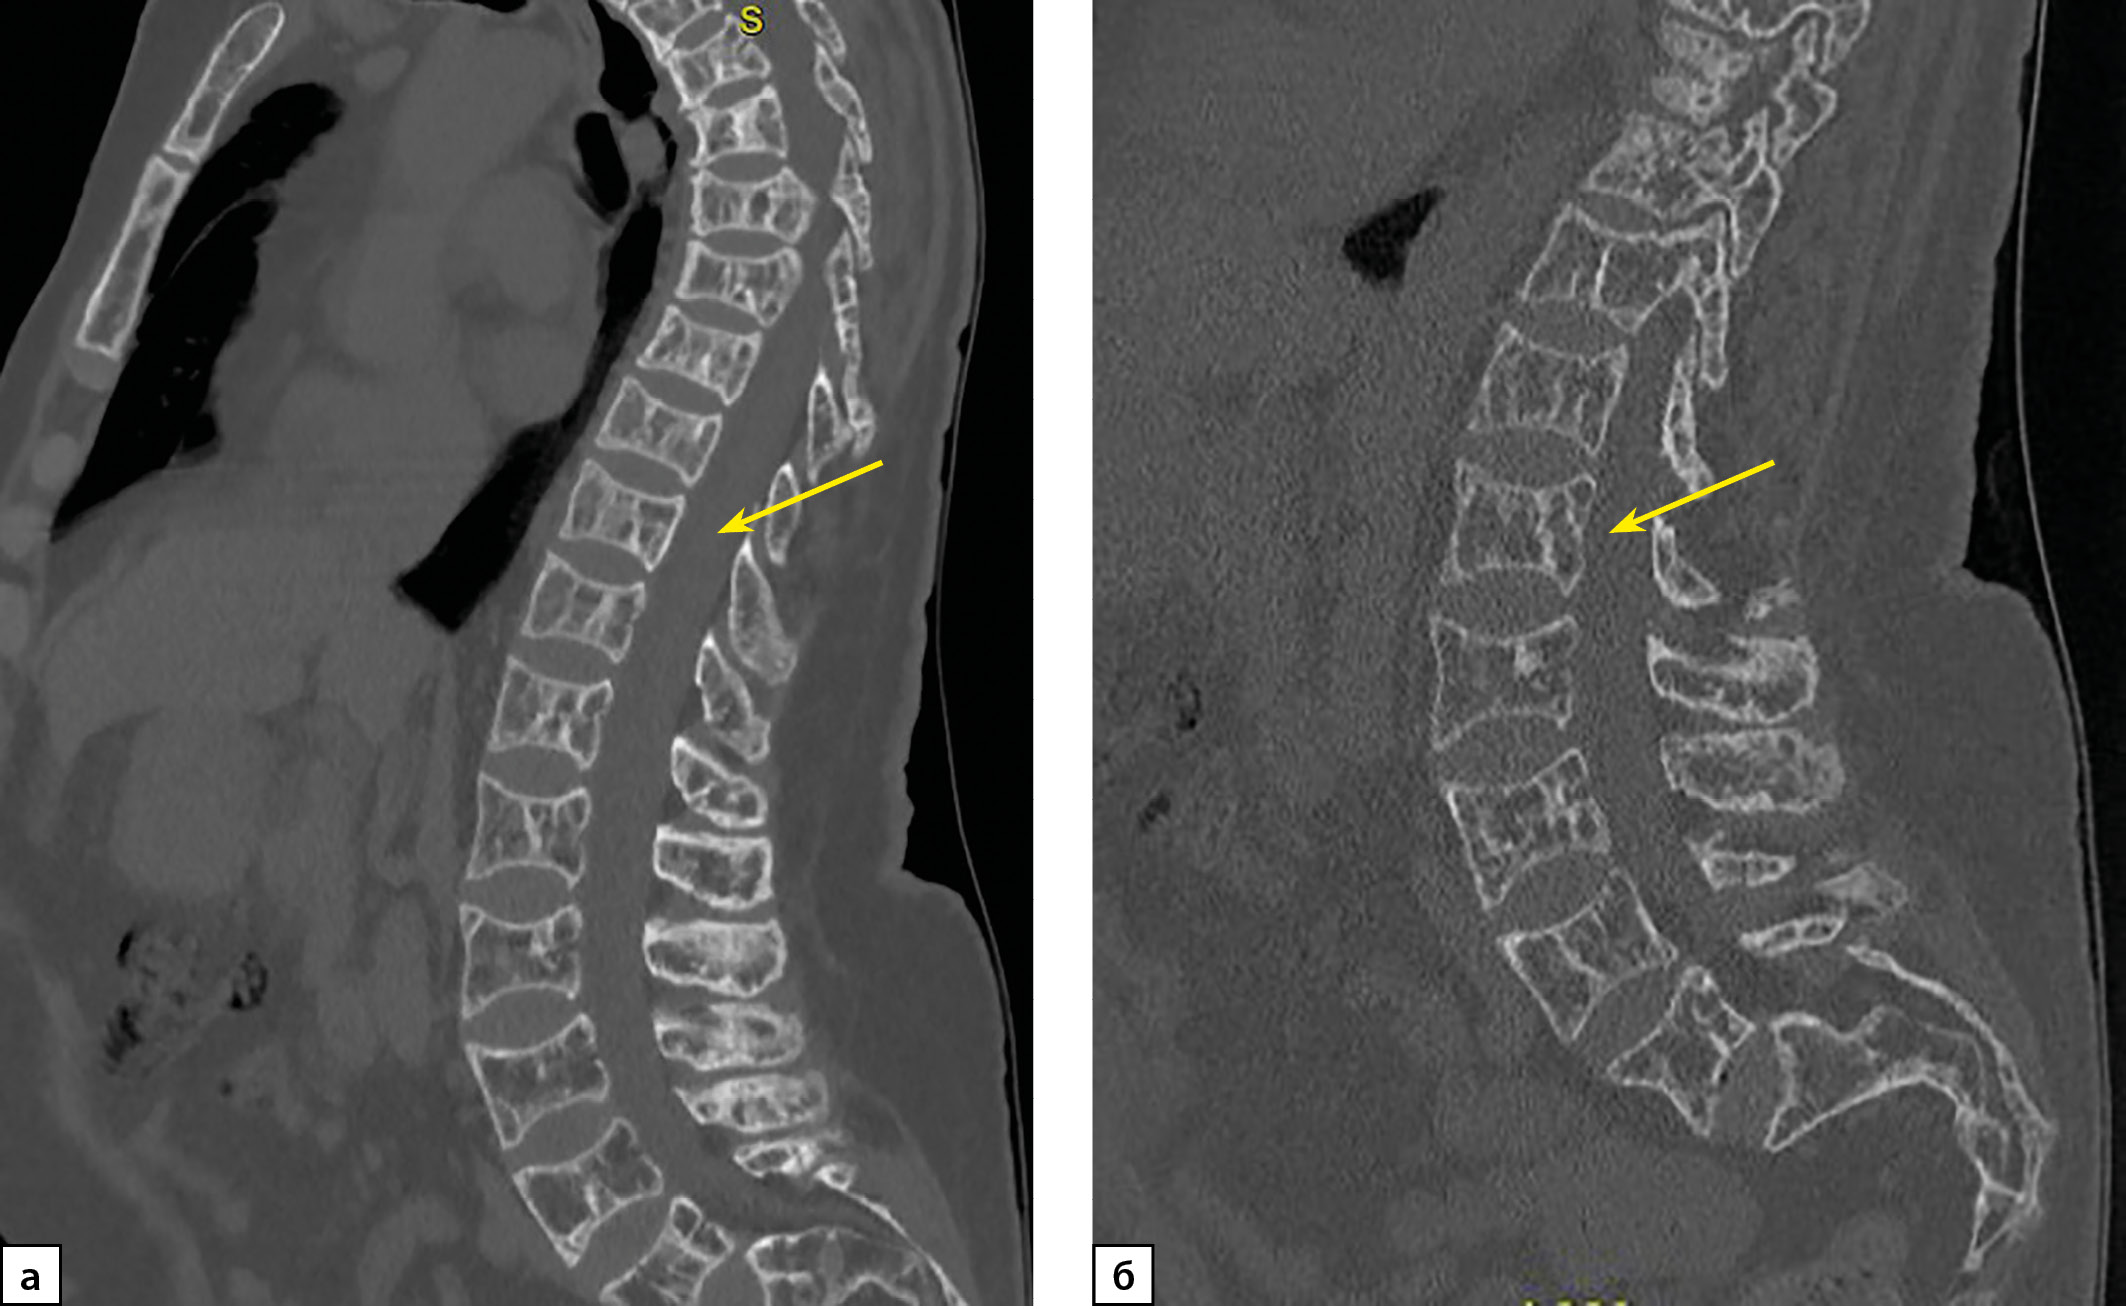

3. Рисунок 3. Пациентка П. КТ исследование позвоночника от 2023 г. а) мультипланарная реконструкция, костный режим. Определяется выраженное (более 40%, 3 ст.) снижение высоты тел позвонков с формированием двояковогнутой их деформации («рыбьи позвонки»). Структура позвонков порозна, с участками кистовидной перестройки. Костные трабекулы утолщены. б) КТ-исследование поясничного отдела позвоночника, сагиттальная проекция. Определяется выраженное (более 40%, 3 ст.) снижение высоты тел позвонков с формированием двояковогнутой их деформации («рыбьи позвонки»). Структура позвонков порозна, с участками кистовидной перестройки. Костные трабекулы утолщены. КТ картина без динамики по сравнению с 2022 г. | |